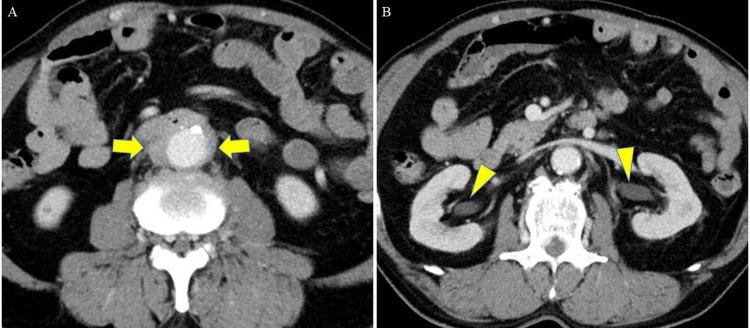

Case Report: Primary aortoduodenal fistula caused by a 30-mm inflammatory abdominal aortic aneurysm.

Primary aortoduodenal fistula (PADF) is a rare but fatal condition with a high mortality rate. Among these, an even smaller subset is caused by an inflammatory abdominal aortic aneurysm (IAAA). Controlling hemorrhage and infection is the primary concern for lifesaving treatments. The standard treatment involves radical open surgery, although endovascular surgery is considered depending on the patient's condition and emergency. Currently, the optimal surgical strategy remains controversial. This study describes the surgical management of a rare case with PADF caused by an IAAA, highlighting challenges in treatment. A 71-year-old man was referred to our hospital following a sudden massive melena. Computed tomography revealed PADF caused by a suspected IAAA. Emergency anatomical reconstruction, fistula closure, and omental coverage via laparotomy were subsequently conducted. After the primary surgery, the patient experienced two episodes of hemorrhagic shock due to infection-induced rupture at proximal and right leg anastomosis sites, which were treated with endovascular repair. The patient was discharged 3 months after the initial surgery. However, 1 month after discharge, a pseudoaneurysm was discovered at the proximal anastomosis site caused by re-infection-induced rupture, and extra-anatomical reconstruction was performed. Excessive surgical invasion caused disseminated intravascular coagulation, and the patient died 1 week postoperatively. The prognosis for PADF management remains poor. Endovascular repair for emergent hemostasis is effective; however, the appropriate timing of radical surgery for prosthetic infection risk is unknown. Therefore, accumulating cases to establish the optimal treatment strategy and surgical timing is essential for improving survival rates.